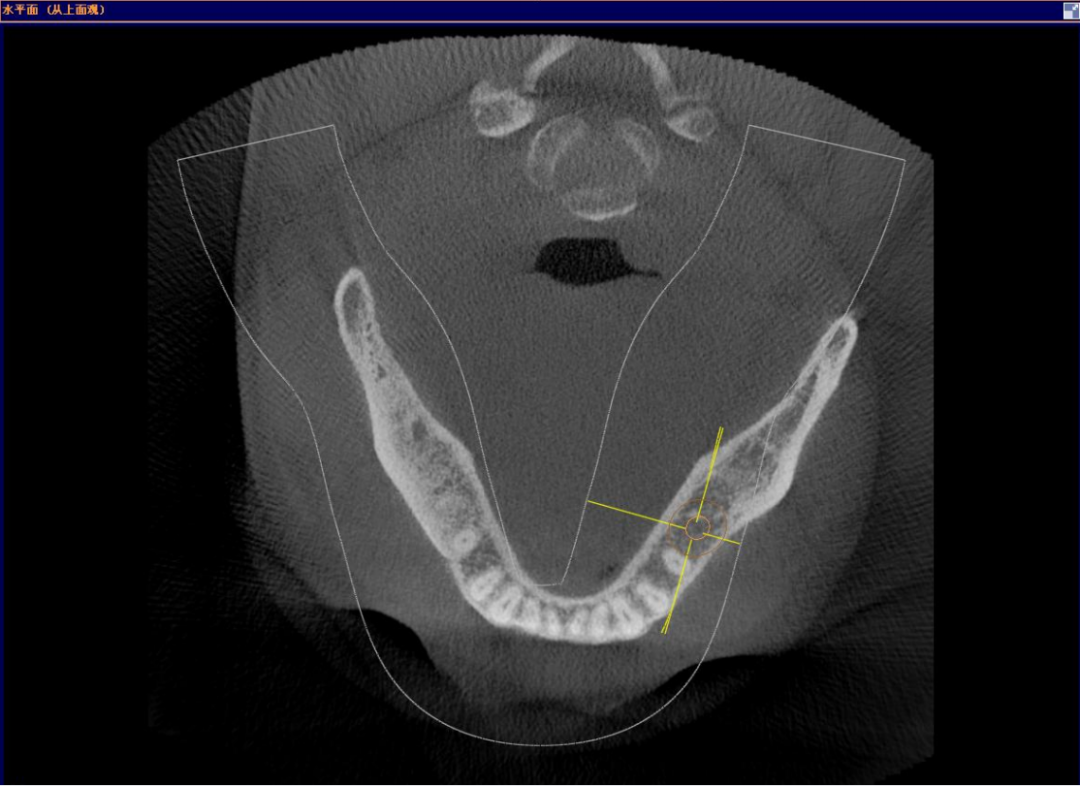

颊舌向宽度约7-8mm,骨质正常,无疏松影,35根尖远中见一"骨岛"影像